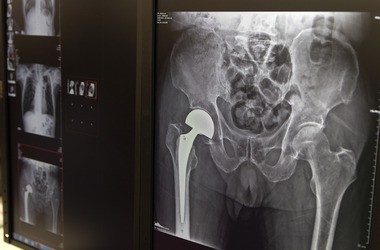

Endoproteza całkowita stawu kolanowego

Całkowita endoproteza stawu kolanowego jest rozważana w sytuacji zaawanasowanych zmian. Ostateczna decyzja zapada zazwyczaj po wyczerpaniu wszystkich innych, nieinwazyjnych sposobów leczenia. Taka operacja kolana polega na zastąpieniu powierzchni stawowej w obrębie kości piszczelowej oraz udowej przez elementy sztuczne, metalowe. Z obszaru rzepki następuje jedynie ewakuacja patologicznych zmian kostnych.